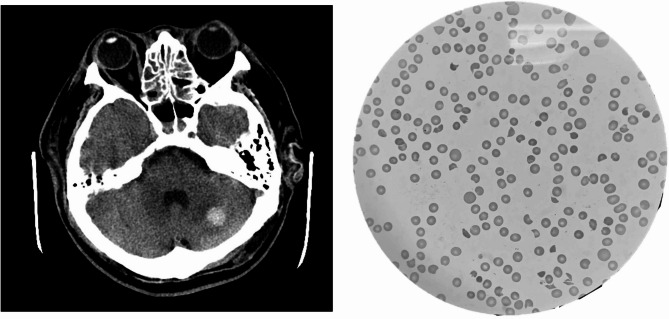

Case presentation: A 37-year-old male with diabetes mellitus presented with typical symptoms of diabetic ketoacidosis. He was managed with an insulin pump and intravenous fluids. However, he developed seizure and progressed to coma, his rapidly deteriorating condition necessitated continuous renal replacement therapy, intubation, and inotropic support. Laboratory data indicated hemolytic anemia and thrombocytopenia, and a blood smear revealed schistocytes. The PLASMIC score was 5, and ADAMTS-13 activity was 2%. The patient was diagnosed with TTP and treated with therapeutic plasma exchange, steroids, and rituximab. His platelet count stabilized above 150,000/µL, and ADAMTS-13 activity progressively improved.